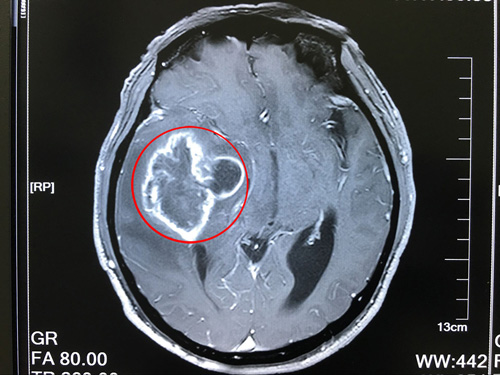

患者术前核磁影像:右侧颞叶占位,右侧高颅压,大脑镰疝

到院后,沈建康教授接待了薛老汉,看了他的影像资料,询问了病史病情后,安排他完善了相关检查。患者住院后,沈教授将患者的病情,手术预后、以及风险和家属做了沟通。他说:胶质瘤是恶性肿瘤,现在患者的胶质瘤已属于3-4级,非常高危,如果不及时做手术,后果将不堪设想。

临床上,CT诊断胶质瘤病较为困难,MRI(核磁共振成像)在发现和显示肿瘤范围方面比CT更为清晰和敏感。手术是治疗胶质瘤的重要手段,其目的是提高患者生存质量和延长生存时间,降低致残率和死亡率。